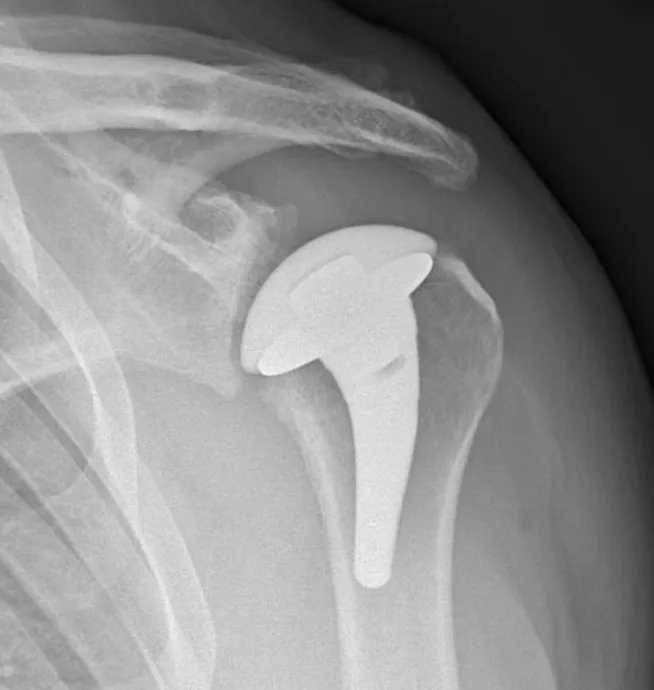

In 2023, Patterson became the first doctor in Iowa to perform a partial shoulder replacement (hemiarthroplasty) using a pyrocarbon humeral head, an implant developed by the medical technology company Stryker and approved by the U.S. Food and Drug Administration in late 2022.

The implant is made of pyrocarbon, a biocompatible material with properties more similar to bone. Pyrocarbon is a lightweight alternative to cobalt chrome, a material commonly used in shoulder replacement surgeries. The pyrocarbon implant’s ball (humeral head) provides stability and less stress on the shoulder socket (glenoid) over time—theoretically reducing the risk of future shoulder problems.

“This implant is thought to wear less aggressively on the socket,” Patterson says. “It’s a really promising implant for younger patients or patients like Michael, who have very high activity levels to maintain. With this implant, there is theoretically less concern about component failure, especially with higher-level activities.”

At a follow-up visit, Patterson showed Donahoo an X-ray indicating that the pyrocarbon implant had settled itself into his shoulder. About a year after surgery, Donahoo says his shoulder is at about 80%, other than lateral movements.